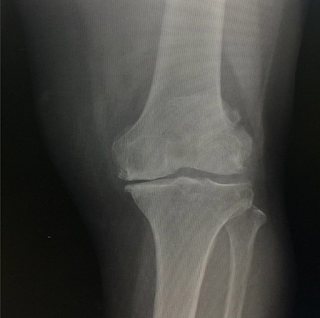

- Fractura subtrocantérica derecha en tejido patológico, 31A3.3 de AO, Cappana-Campanacci clase 2.

- Reducción Abierta y Fijación Interna con clavo de reconstrucción tipo DLT 200x100 mm con tornillo proximal 90 mm y distal cortical 6.5 mm x 30 mm.